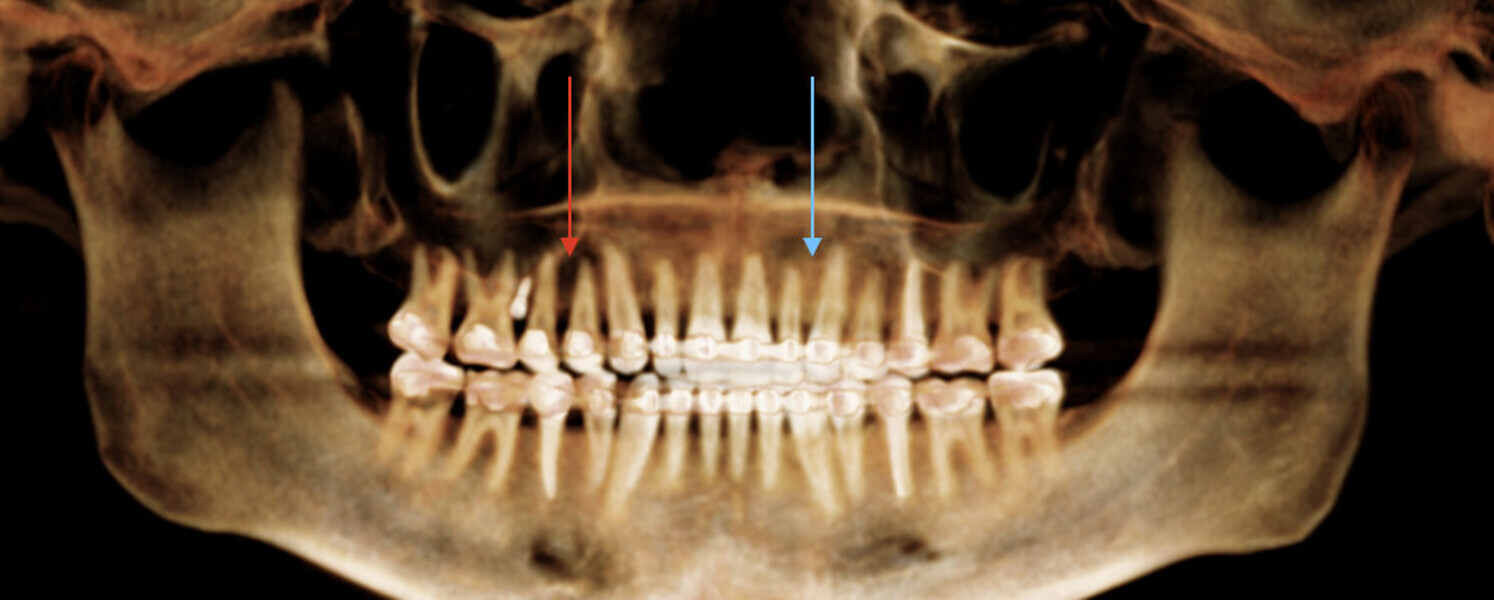

New Age orthodontics and orthopaedics with temporary anchorage devices